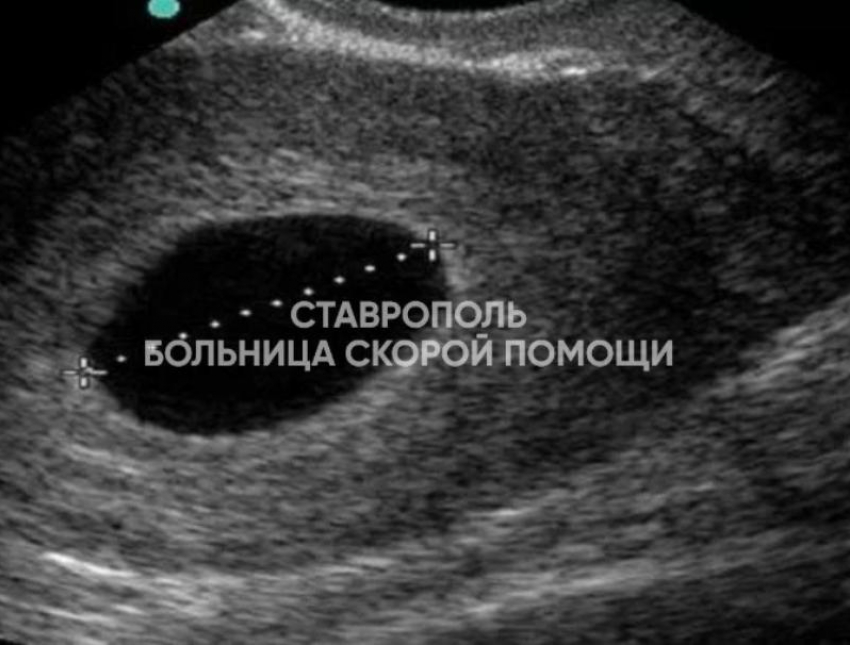

Женщина обратилась к врачам из-за задержки менструального цикла. Доктора провели УЗИ и увидели в полости матки плодное яйцо, однако эмбрион в нем отсутствовал. Установили диагноз — анэмбриония (неразвивающаяся беременность по типу пустого плодного яйца).